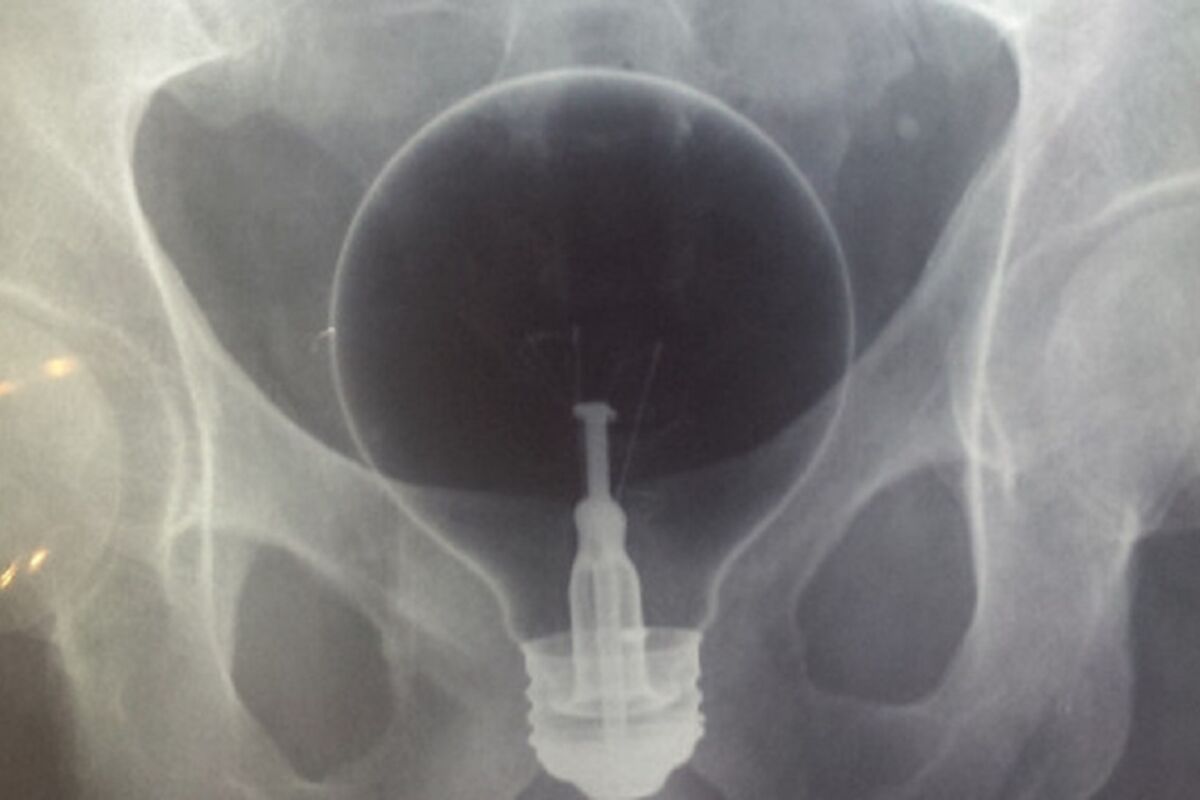

TOTALNO UVRNUTO: 22 predmeta koje su ljudi uspeli da izgube u svojim zadnjicama! (FOTO)

Ovo su fotografije koje verovatno nikada nećete moći da zaboravite. Ovim ljudima je svašata palo na pamet, pa su tako različiti predmeti završili u njihovom stomaku.